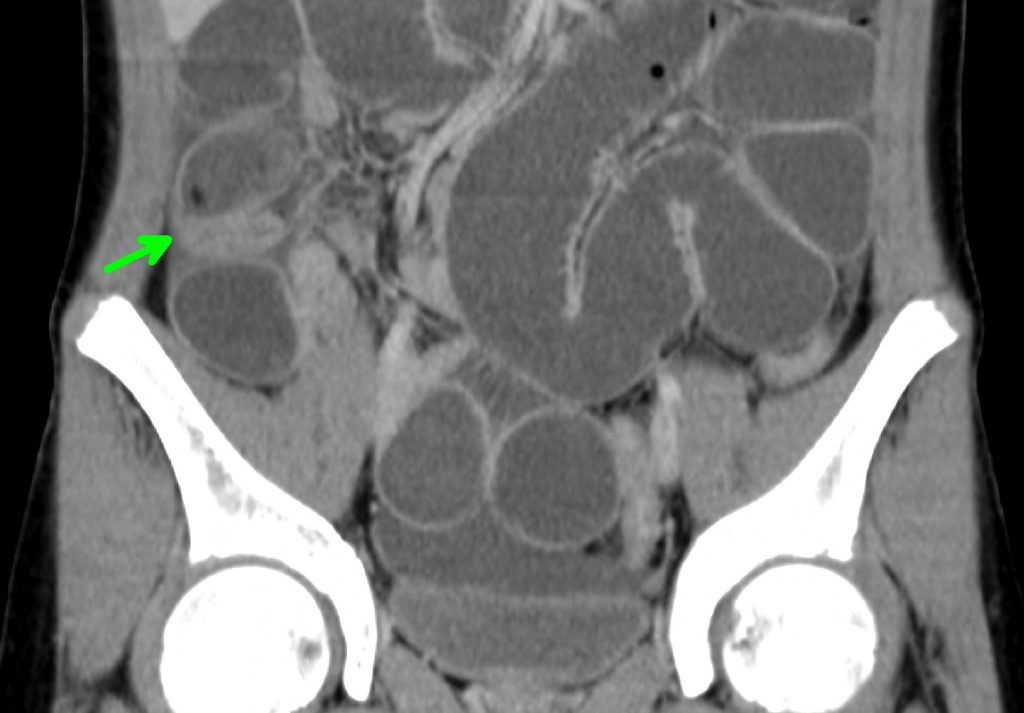

兒童腸胃科醫師何珮瑜指出,住院2天後症狀並無明顯的改善,仍然無法進食且持續嘔吐,肚子痛也還是持續,因為肚子仍然很脹,且病況持續,主治醫師決定作腹部的電腦斷層看看肚子裡的情況。

結果在腹部電腦斷層顯示,小腸中有異物卡住,緊急會診兒童外科醫師王國強,經過手術的處理,發現1顆完好的香菇卡在腸子中,造成腸子阻塞,食物完全無法通過腸道,經過手術的移除後,方小弟終於不會嘔吐腹痛,開心的回家了。